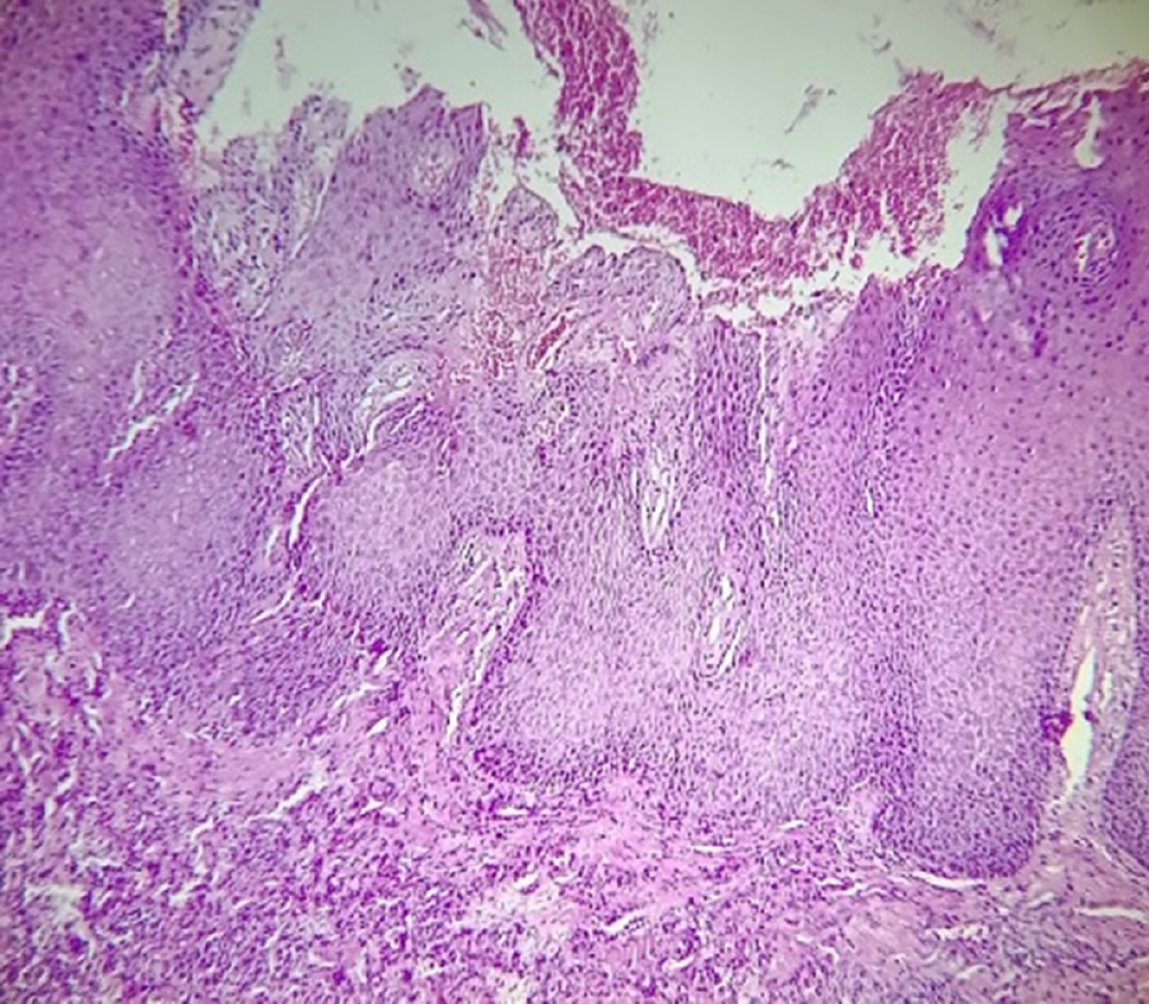

Figure 3 Histopatological image.

A: A lesion characterized by the presence of a stratified squamous epithelium parakeratinized with acanthosis and thick and elongated epithelial processes, which give a papillomatous appearance. In some areas, mitosoid and koilocytic figures are observed (50 ×). The connective tissue was well vascularized and free of injury; B: Mitosoid and koilocytic figures (200 ×).